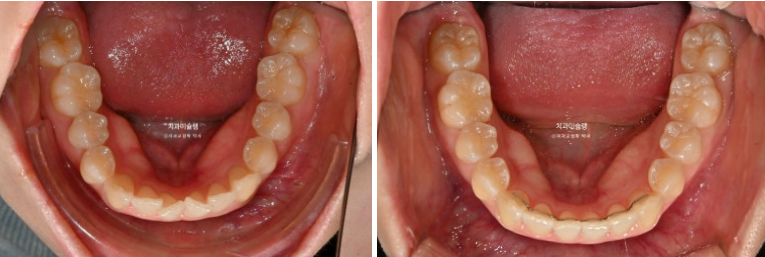

거미스마일 소량 개선되었습니다.

앞니 높낮이는 완벽한 대칭을 이루고 아랫입술과 조화로운 호를 그립니다.

25.01~25.11

미소가 깔끔해졌습니다.